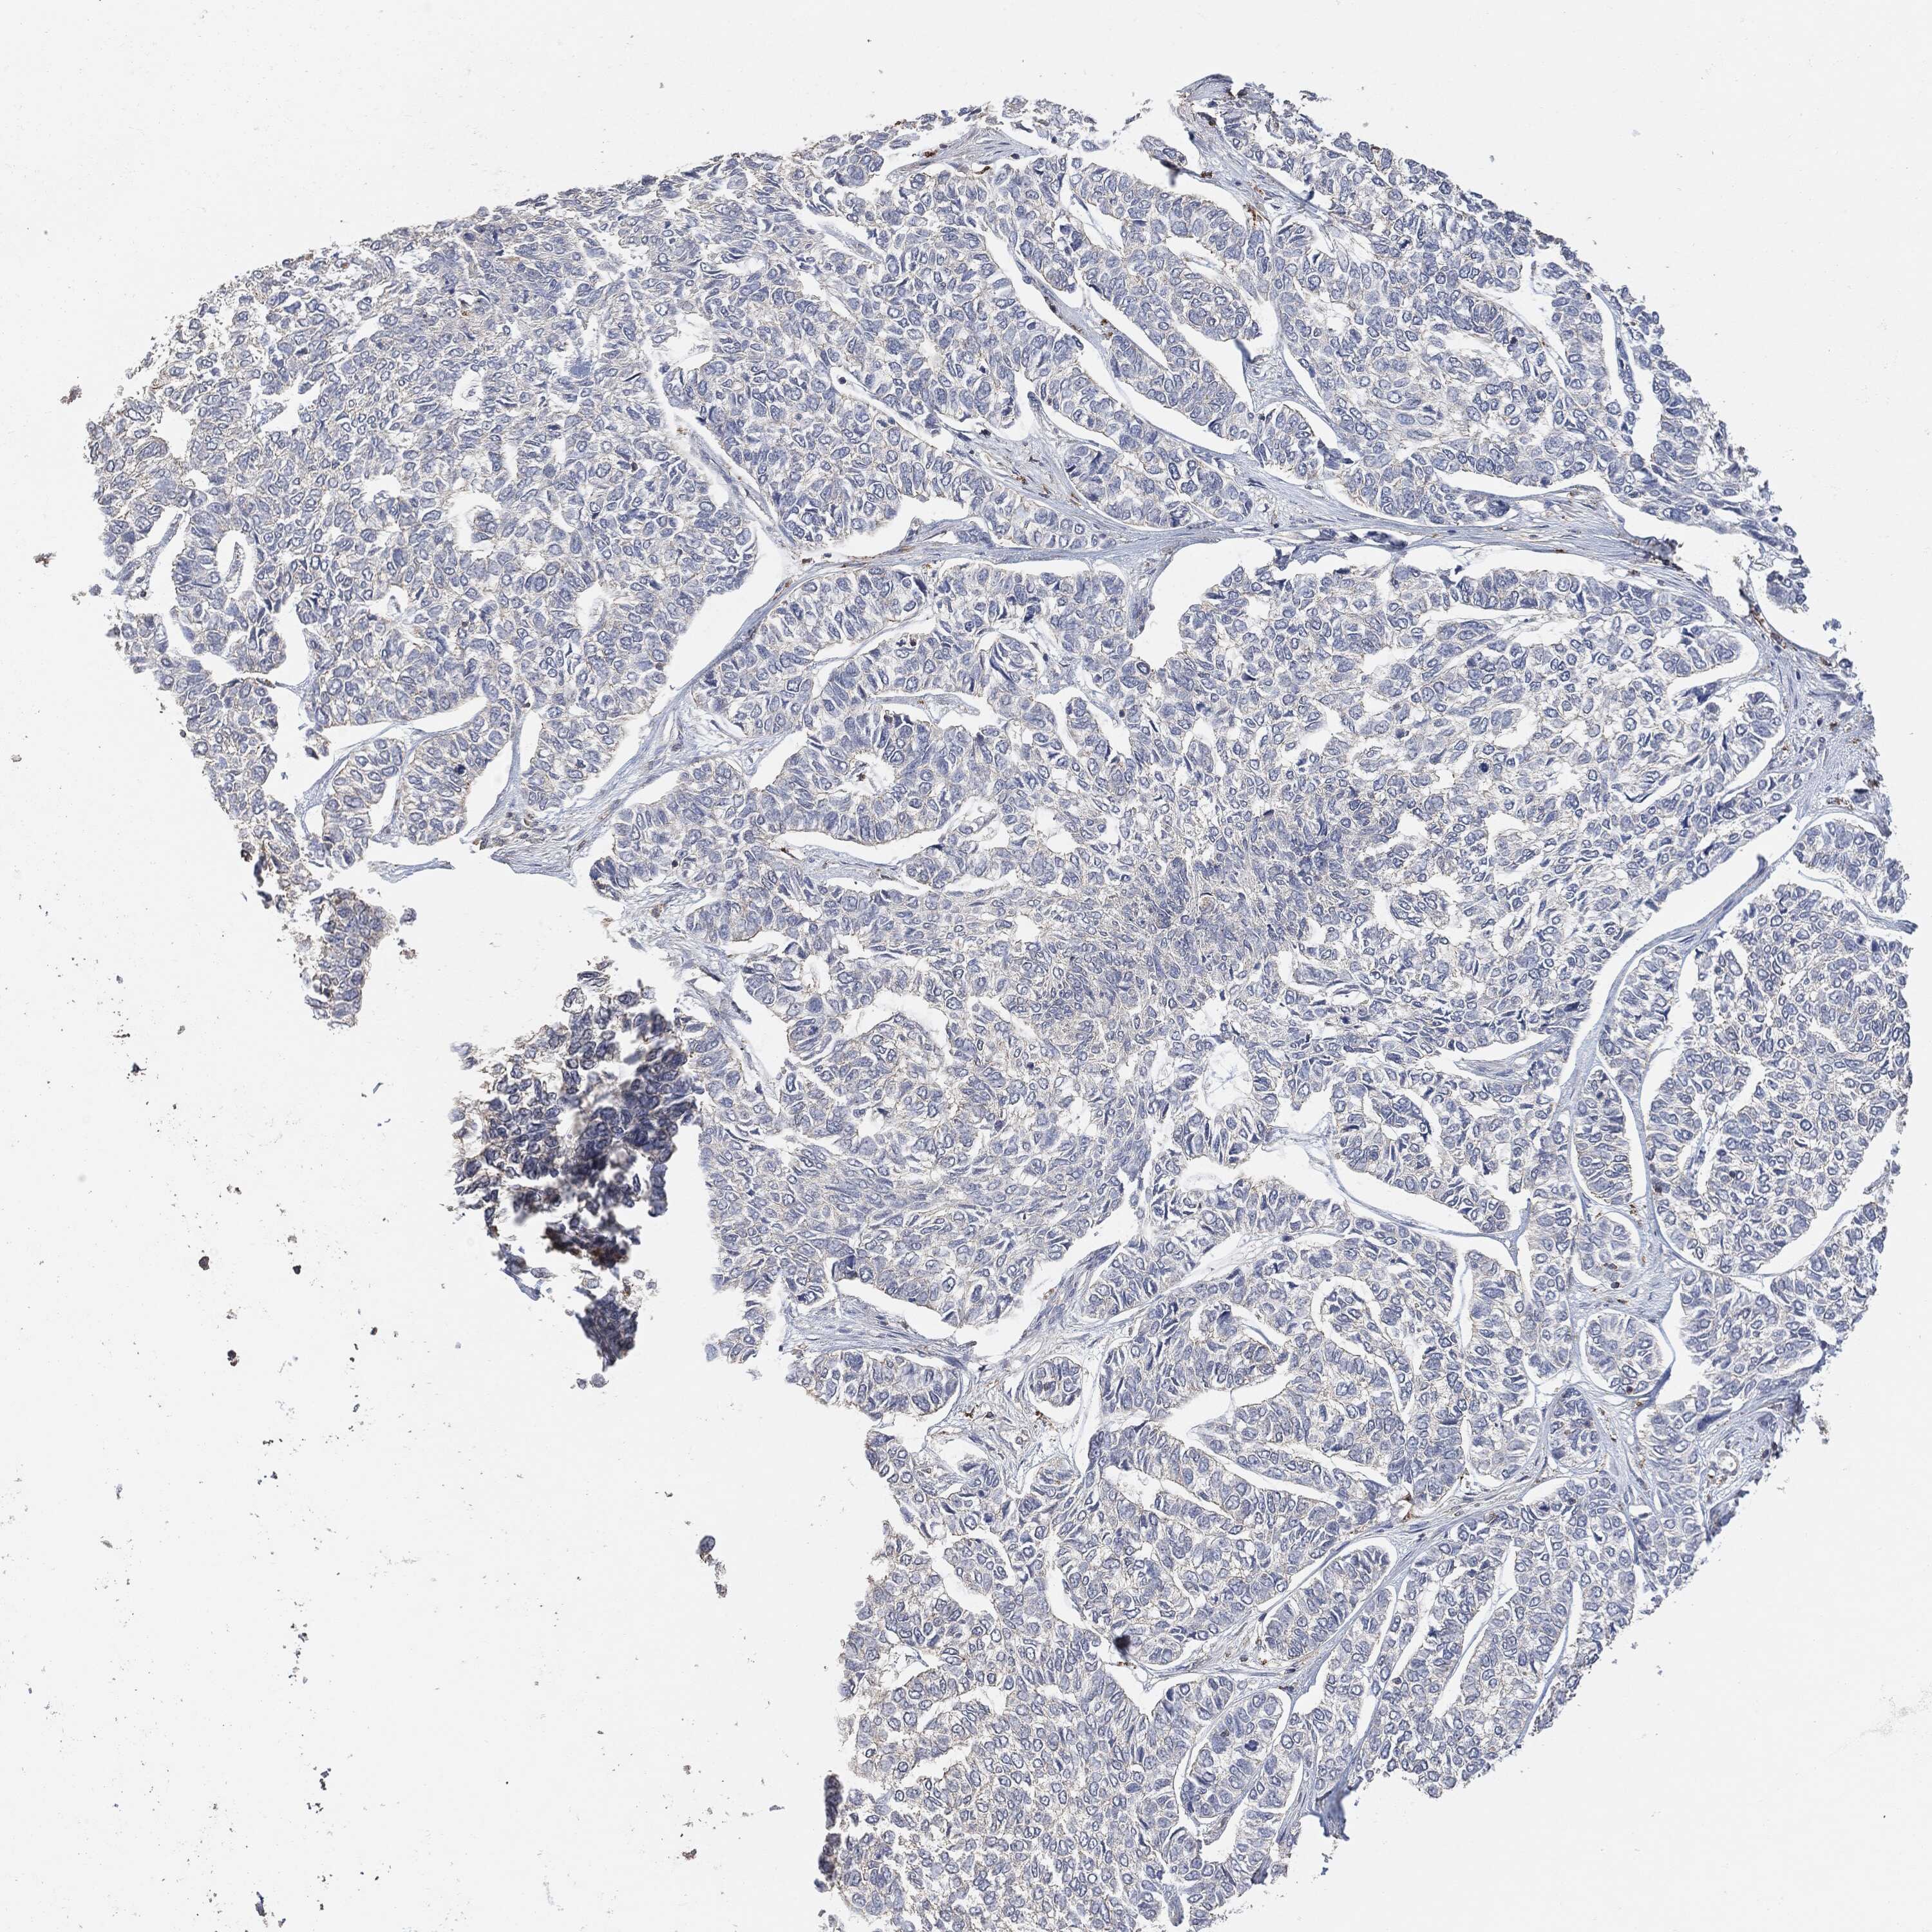

SKIN CANCER - Protein expressioni

A mouse-over function shows sample information and annotation data. Click on an image to view it in a full screen mode. Samples can be filtered based on level of antibody staining by selecting one or several of the following categories: high, medium, low and not detected. The assay and annotation is described here.

Antibody stainingi

Antibody staining in the annotated cell types in the current human tissue is reported as not detected, low, medium, or high, based on conventional immunohistochemistry profiling in selected tissues. This score is based on the combination of the staining intensity and fraction of stained cells.

Each image is clickable and will lead to virtual microscopy that enables deeper exploration of all samples and also displays staining intensity scores, fraction scores and subcellular localization as well as patient and tissue information for each sample.

Squamous cell carcinoma, NOS